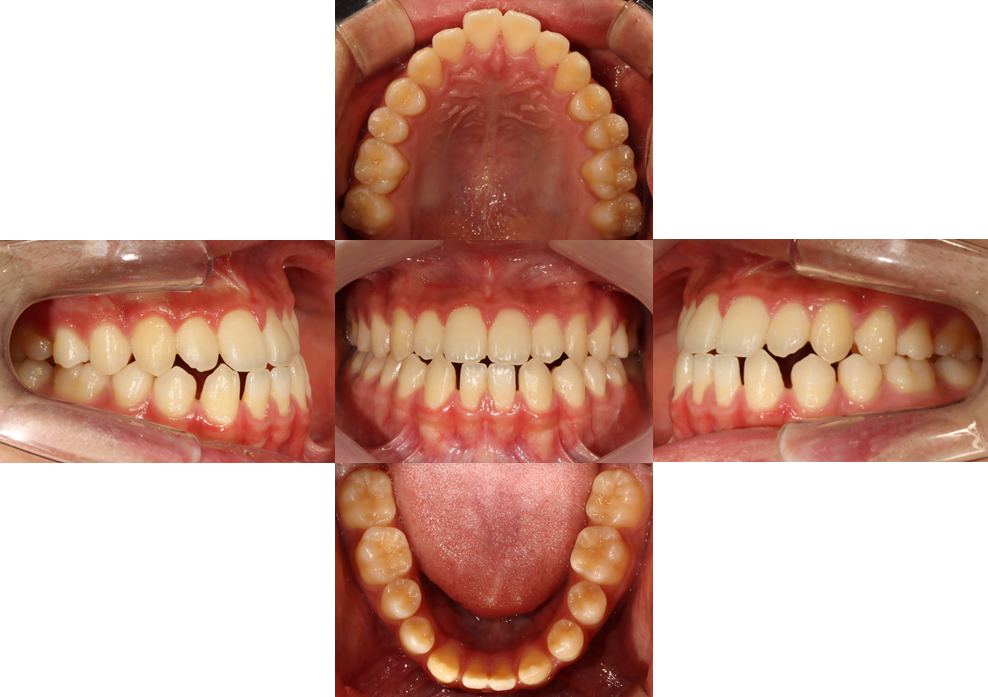

전체 교정 치료 #4

작성자

최고관리자

조회

703

작성일

23-08-07